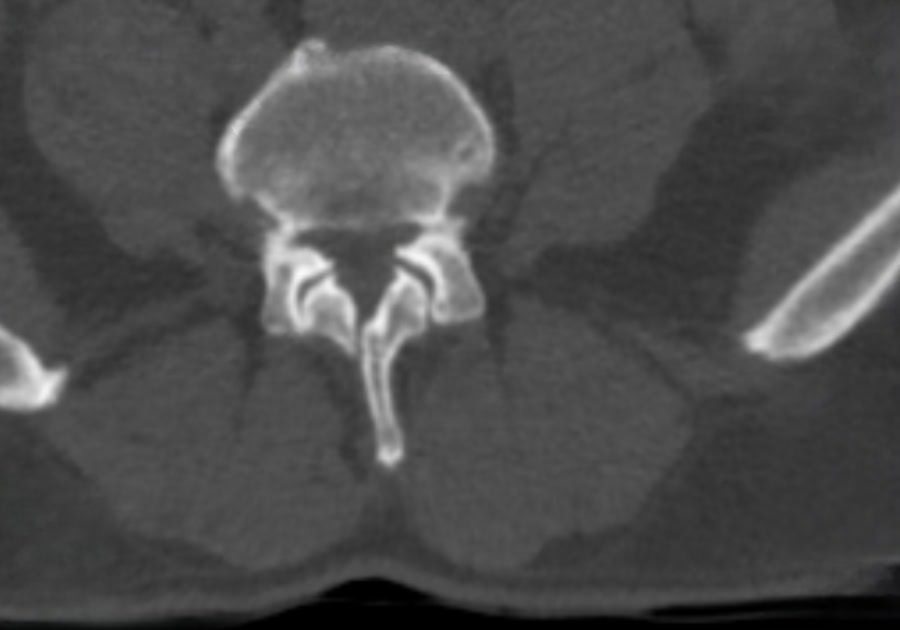

Preop.